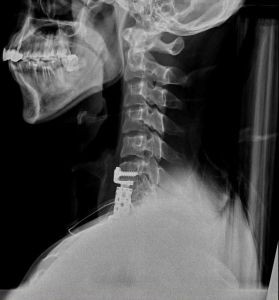

左圖:洪祥益醫師表示,大多數頸椎手術都可以用前側開刀的方式進行。

右圖:洪祥益醫師利用鈦金屬人工椎體為小瑞進行頸椎重建。

洪祥益醫師表示,當初在急診看到小瑞的時候,因為他的頸椎爆裂性骨折,造成脊髓腔、神經都受到壓迫,一般正常人肌力測試應該是五分,但是當時小瑞的肌力測試只有一分,用一般通俗的說法來說,就是頸部以下幾乎全部癱瘓,而且還伴隨著嚴重的神經痛。所以,第一步就是要先進行脊髓減壓術,清理壓迫脊髓及神經的碎骨,再用鈦金屬人工椎體,進行頸椎重建術。

術後隔天恢復生活活動能力,接著觀察一周就康復出院,小瑞跟家人都說,沒想到這麼快就能恢復。洪祥益醫師表示,一般人會以為脊椎在後背,所以,受傷都要從後背開刀,但從神經外科醫師的角度來看,大部分的頸椎問題都可以從前側開刀,而且前側開刀可以不用燒開肌肉,直接進行手術,減少肌肉、神經受損的可能性,除了降低風險也能縮短恢復期。現在小瑞只需要帶著頸圈大約兩個月後,就可以進行輕便的工作,等到六個月後鈦金屬人工椎體跟自體頸椎骨融合,就能恢復正常的生活與工作。